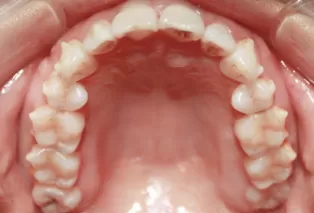

Photos intra-orales